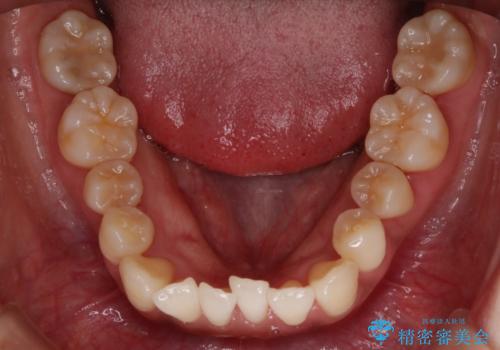

【非抜歯】左右の八重歯・前歯の反対咬合の改善 インビザライン

- 前歯のガタつきを主訴にご来院されました。

診査の結果、骨の厚みに余裕がなく幅の拡大とIPR(歯と歯の間を削り隙間を作る作業)のみでは歯周病に対する不安が残ることが懸念されたため、マイクロインプラントを用いて奥歯から順にすべての歯を後方移動させる方法によってスペースを作ることとなりました。